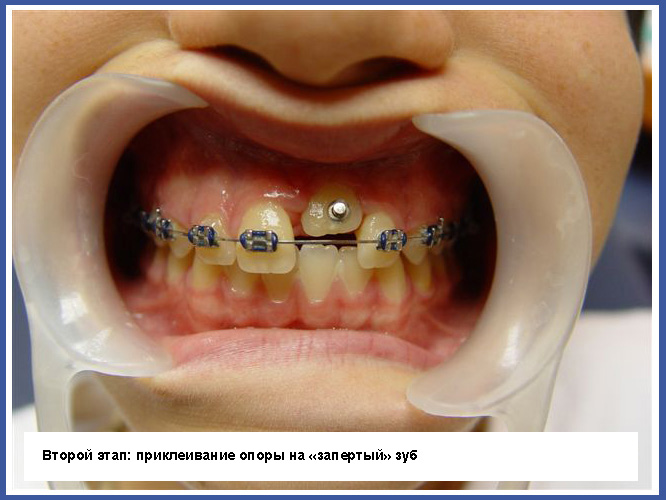

3.Если зуб «заперт» вследствие того, что траектория прорезывания неправильная, нужно обнажить «запертый» зуб хирургическим путем. Иногда простое обнажение зуба может изменить траекторию прорезывания, а иногда во время обнажения нужно приклеивать ортодонтическое приспособление на «запертый зуб» и активно вытягивать его на зубную дугу.